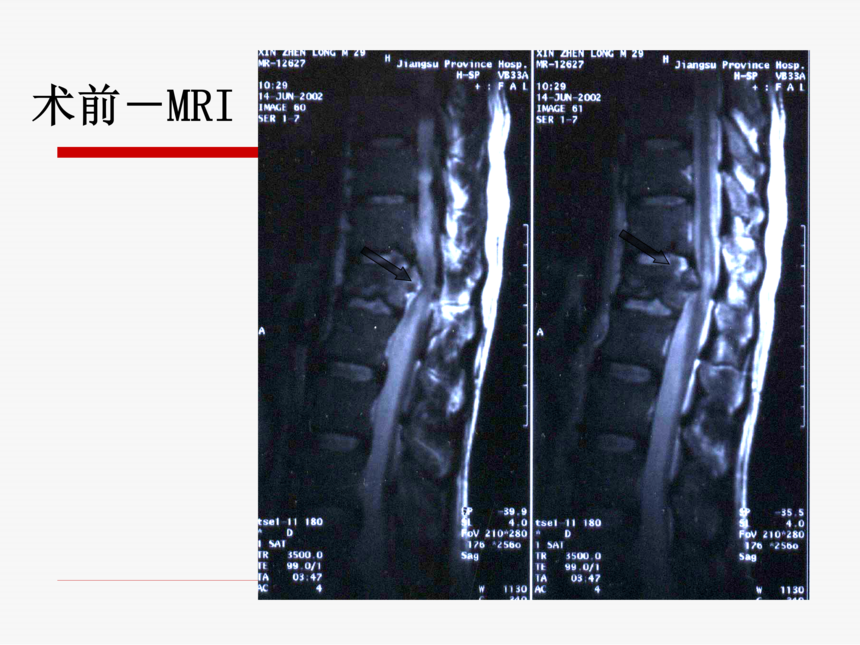

脊髓损伤后早期康复训练